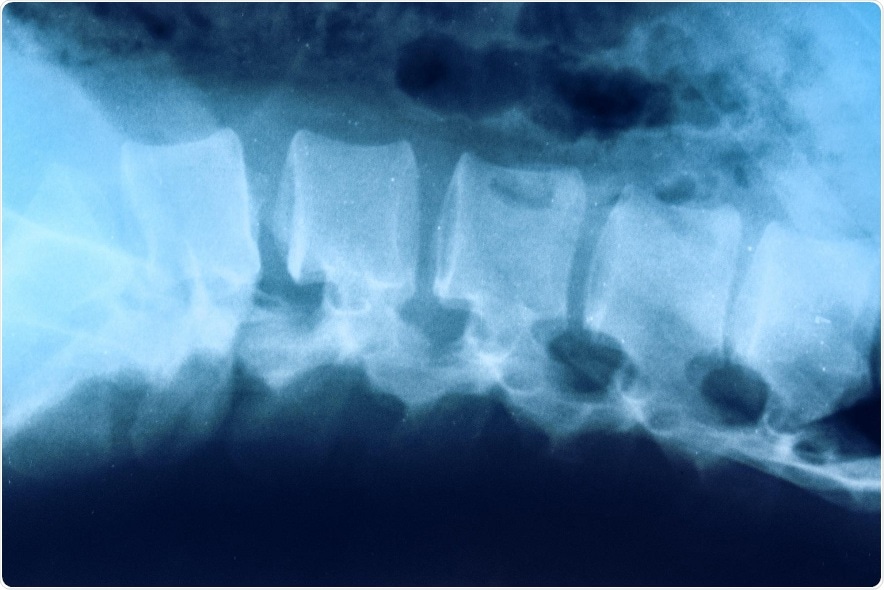

Two top scientists at the University of Virginia School of Medicine are seeking answers to questions about spinal cord injuries that have long frustrated the development of effective treatments.

The UVA scientists are working to understand why critical nerve cells called neurons continue to die after spinal cord injuries.

The scientists, Jonathan Kipnis, Ph.D., and Kodi Ravichandran, Ph.D., are teaming up to understand why critical nerve cells called neurons continue to die after spinal cord injuries. So little is known that doctors aren’t even certain if the body’s immune response is beneficial or harmful.